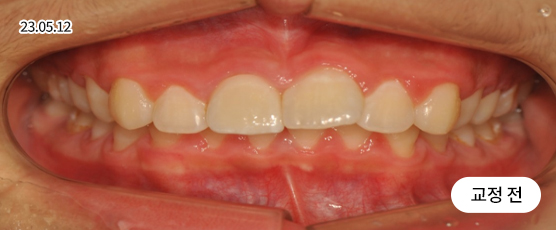

벌어진 치아교정 Solution

치아 벌어짐이 전체적으로 있는지 또는 부분(앞니 등)에만 있는지를 진단하고,

교정 장치를 부착하고 빈 공간으로 치아를 이동시켜 맞춰주는 방법으로 치료합니다.

* 본 사진은 동일 조건에서 촬영되었으며, 환자 본인의 동의를 얻어 게재되었습니다.